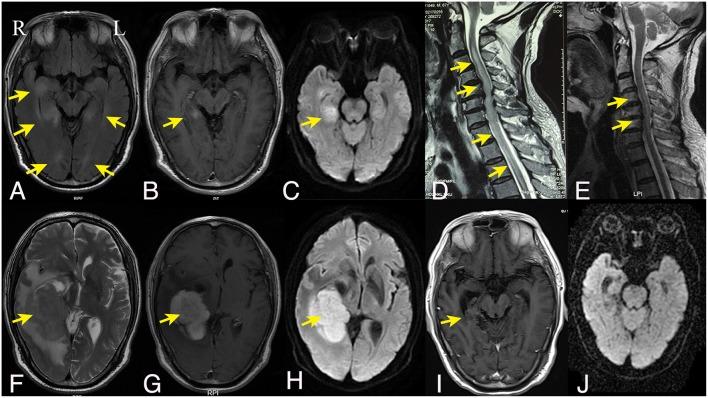

Identifying lymphoma as the cause of neurological disease is diagnostically challenging when the clinical manifestations are atypical. We report an unusual case of a previously healthy immunocompetent 67-years-old man presenting with acute onset of symptoms of myelopathy and mild personality changes. Magnetic resonance imaging (MRI) revealed multifocal periventricular lesions and longitudinally extensive transverse myelitis (LETM). He had very good response to corticosteroids and was in remission for over 6 months. Repeat MRI showed an unexpected mass lesion in the brain which was later confirmed by brain biopsy as diffuse large B cell lymphoma. Subsequent FDG-PET/CT revealed systemic disease with lymphonodal and testicular manifestations (Stage IV disease). It is therefore important to consider lymphoma as a differential diagnosis in patients with LETM and demyelinating lesions in the brain.

当临床表现不典型时,将淋巴瘤确定为神经疾病的病因在诊断上具有挑战性。我们报告了一例不寻常的病例,一名67岁既往健康的免疫功能正常男性,急性起病,出现脊髓病症状和轻度人格改变。磁共振成像(MRI)显示多灶性脑室周围病变和纵向广泛横贯性脊髓炎(LETM)。他对皮质类固醇反应良好,缓解超过6个月。复查MRI显示脑部意外出现肿块病变,后来经脑活检证实为弥漫性大B细胞淋巴瘤。随后的氟代脱氧葡萄糖正电子发射断层扫描/计算机断层扫描(FDG-PET/CT)显示存在系统性疾病,伴有淋巴结和睾丸表现(IV期疾病)。因此,对于患有LETM和脑部脱髓鞘病变的患者,将淋巴瘤作为鉴别诊断是很重要的。